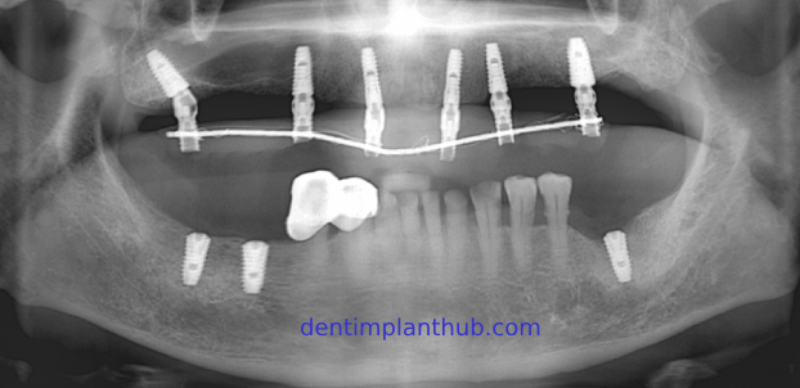

Case 1: Maxilla all - on - 6 & 36, 45, and 46.